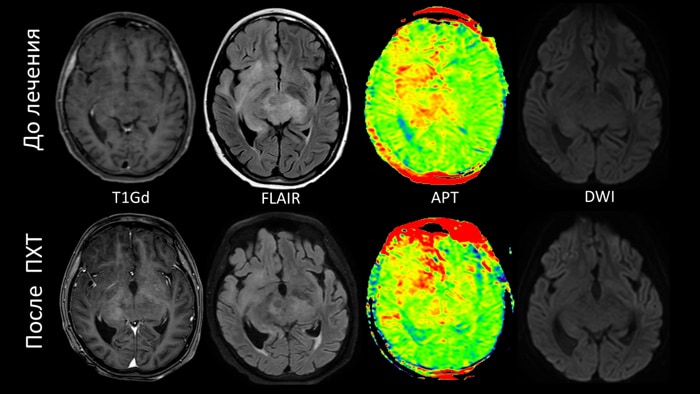

Случай №2 Пациент с биталамической глиобластомой- на контрольном МР-исследовании после проведенного лечение, на изображениях FLAIR и постконтрастных T1-ВИ без явной положительной динамики. Однако на АPT-картах определяется выраженное уменьшение интеснивности сигнала, что говорит о положительном терапевтическом эффекте.